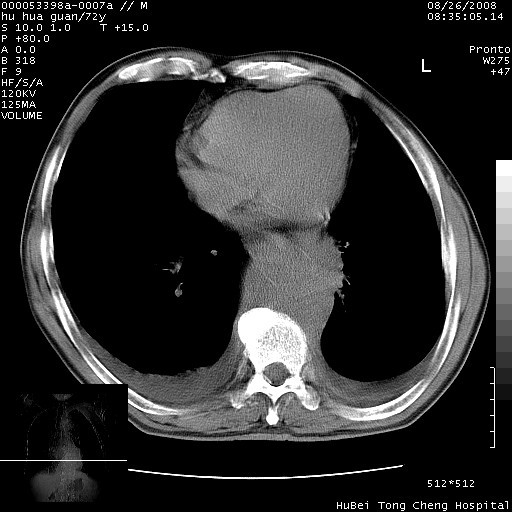

考虑胸主动脉下段夹层破裂。

考慮夾層動脈瘤破裂可能,建議增強掃描。

可以明确的说。肯定不是主动脉夹层破裂出血!考虑为淋巴瘤或间叶组织来源的恶性肿瘤可能性大。右肺小结节建议薄层观察,如能发现恶性征象,那椎前改变就考虑为转移所致。至于双侧少量胸水乃静脉血回流受阻所致。

降主动脉前移位,后纵隔占位

后纵隔占位,降主动脉前移位;双侧胸腔积液;应排外食管病变侵犯血管可能;

主动脉瘤破裂